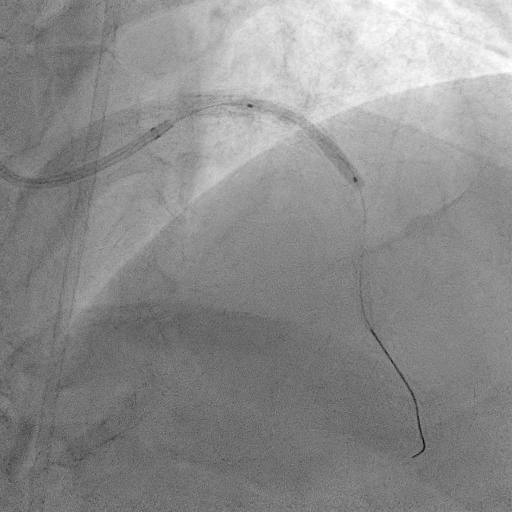

The procedure commenced with EBU 3.5/6F catheter and CTO wire with microcatheter. Managed to cross the lesion and changed to workhorse wire. Proximal LAD ISR predilated with SC balloon 2.0/15mm. CTO at mid segment predilated with same balloon. However, noted perforation at mid LAD after predilatation. We used the same balloon to tamponade the perforation and attempted to wire down distal LAD with another wire but failed. Right femoral puncture was performed and another EBU3.5/6F was used. The ping pong technique was used in which another workhorse wire to distal LAD when tamponade balloon was deflated. However, the covered stent was unable to cross the proximal LAD. Proximal segment was then predilated with NC 2.5/15mm, yet still unable to advance the covered stent. Subsequently, guide extension GuidePlus II was used and managed to advance covered stent 2.5/20mm. Tamponade balloon was then removed and covered stent deployed at perforation site. We proceeded with drug coated balloon angioplasty to proximal-mid LAD using DCB 3.5/20mm. Patient was stable and bedside echo revealed minimal pericardial effusion only

Coronary artery perforation is rare but potentially lethal complication. Early recognition and immediate balloon occlusion are crucial in preventing cardiac tamponade and haemodynamic compromise. Double catheter guide technique (ping pong) allowed controlled delivery of covered stents to perforation site. It ensures uninterrupted balloon occlusion of perforated site and smooth delivery of bulky covered stents.